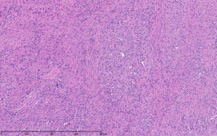

As part of the patient’s treatment, the thoracic surgery team performed a right middle and lower lobectomy. A 4-cm mass in the right bronchus intermedius without invasion into the lung parenchyma was revealed, and pathology confirmed the diagnosis of leiomyosarcoma. The sections of pulmonary tissue from the right middle and lower lobectomy showed a spindle cell tumor most consistent with leiomyosarcoma (Figure 3a-d). Most of the tumor was low grade, with some foci showing high-grade nuclear atypia and increased mitotic activity. Despite these rare mitotic figures, there was no evidence of necrosis. Following surgery, chemotherapy was planned for the patient. However, the patient’s postoperative course was complicated by persistent hypoxic respiratory failure, hypovolemic and hemorrhagic shock, and acute kidney injury. Her respiratory status continued to decline, and she went into cardiac arrest with pulseless electrical activity. She was resuscitated; however, her shock and respiratory failure worsened despite aggressive therapy. Her family chose to transition her to comfort care, and the patient died.

The immunohistochemistry staining also lent additional support to the diagnosis of leiomyosarcoma. As would be expected for such a diagnosis, both vimentin and desmin were immunoreactive. The tissue also stained positive for muscle markers including smooth-muscle actin, muscle-specific actin, and desmin, thus supporting the histological diagnosis of low-grade (highly differentiated) leiomyosarcoma. The tissue stained negative for S100, therefore pointing away from melanoma as a potential diagnosis. The immunohistochemistry profile also included pankeratin staining to distinguish a potential carcinosarcoma with sarcomatoid differentiation, and this test result returned negative.

The patient’s malignancy followed the typical behavior of endobronchial leiomyosarcoma. These tumors are expected to expand locally, although there was no evidence that her tumors had yet reached this stage of invasion. After lobectomy, surgical pathology of the mass obstructing the bronchus intermedius demonstrated that the tumor had not invaded the visceral pleura, nor were there positive margins at the bronchial, vascular, or parenchymal margins. The tumor was 1 cm from the closest margin. Also in alignment with the diagnosis of a low-grade leiomyosarcoma, there was no evidence of malignant spread to any of the 4 lymph nodes histologically examined, and Ki-67 staining highlighted less than 5% of cell nuclei in the right lung mass and less than 1% of cell nuclei in the left lung mass. Her tumor staging was pT3 pN0.